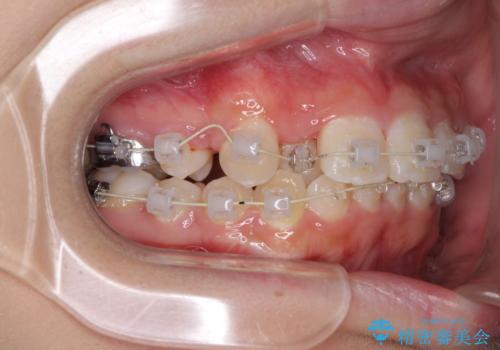

- 八重歯やデコボコをインビザラインで治療したいとのことで来院された患者様です。

インビザライン単体で治療を行うには叢生が強いと判断されたため、事前にワイヤー装置で抜歯矯正を行い、ある程度改善してからインビザラインにて仕上げていくこととしました。